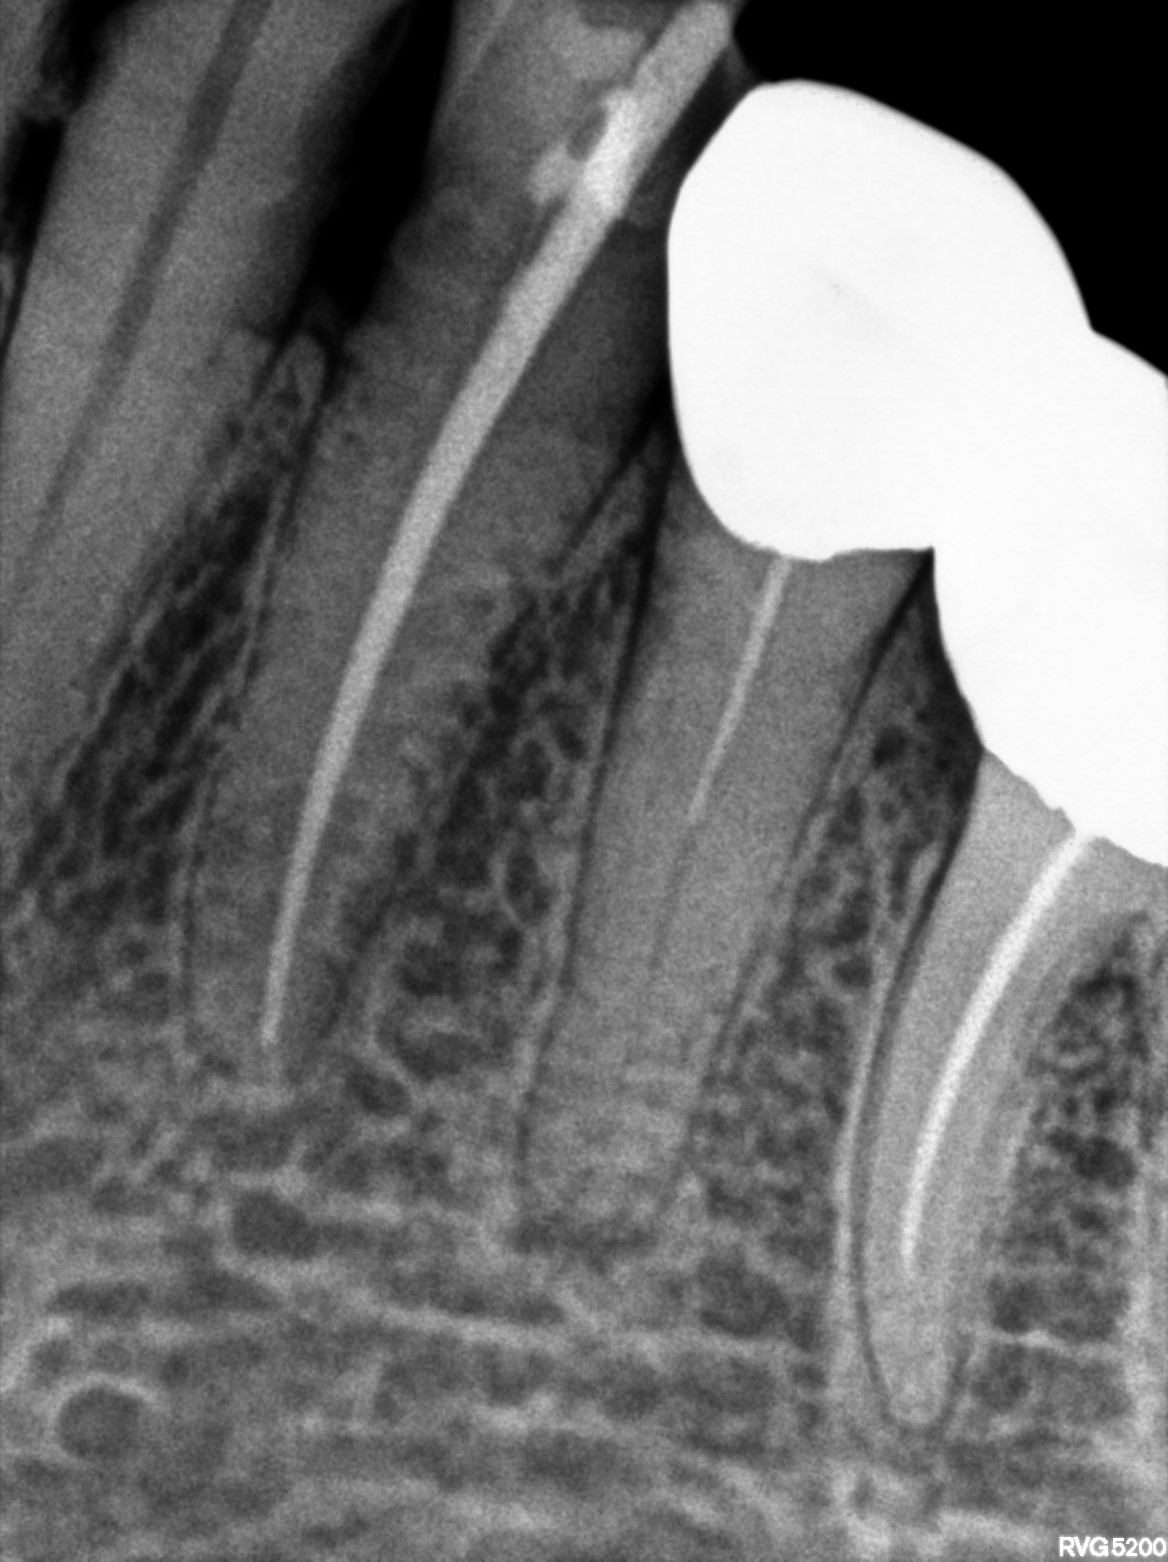

Dental Radiographs FHIR: DocumentReference · LOINC 24641-7

d (12).jpg

24641-7